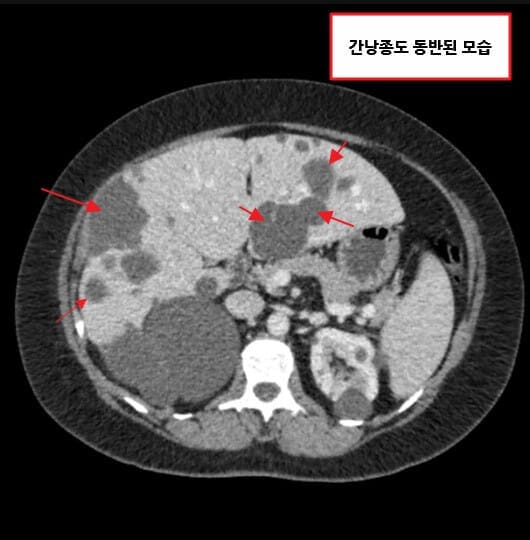

다낭성 신질환 (Polycystic Kidney Disease)

[특징]

양측 신장에 다수의 낭종으로 신장이 비대해지고, 조기 고혈압과 통증·혈뇨·감염이 잦습니다.

간낭종, 두개강내 동맥류, 판막질환 등 신외 합병증이 동반될 수 있습니다.

다낭성 신질환 (Polycystic Kidney Disease, PKD)

양측 신장에 다수의 낭종

조기 고혈압 및 신기능 저하

간낭종, 뇌동맥류 등 신외 합병증 동반

[정의]

다낭성 신질환은 유전적 이상으로 인해 신실질에 다수의 낭종이 발생하여 점차 커지고, 결국 신장이 비대해지면서 만성 신부전으로 진행하는 질환입니다.

– 간낭종, 뇌동맥류 파열 등 신외 합병증이 발생할 수 있습니다.

[진단]

– 신장 초음파에서 다수의 낭종을 확인하여 진단합니다.

– CT/MRI에서 낭종의 분포와 크기를 정밀하게 평가하며, 총신장용적(TKV)을 측정하여 예후를 예측합니다.

[치료]

– 혈압 조절(ACEi/ARB)과 염분 제한이 중요합니다.

– 진행 위험군에서는 Tolvaptan을 고려할 수 있으며, 간기능을 정기적으로 확인해야 합니다. (간낭종 포함 )

– 낭종 감염 시 지용성 항생제를 사용합니다.

– 말기에는 투석 또는 신장이식이 필요합니다.